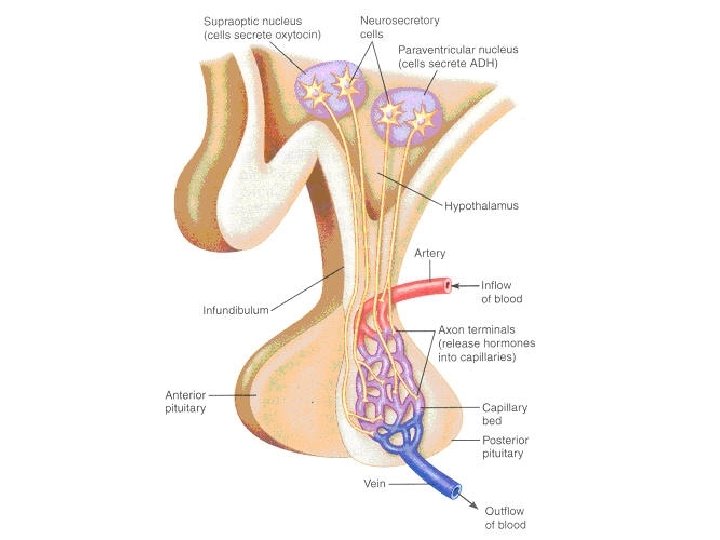

Hypothalamus – funkce Hypothalamus • ncl. suprachiasmaticus – centrum cirkadiálních rytmů • ncl. supraopticus + paraventricularis (magnocelulární neurony) – ADH (vazopresin) + oxytocin • ncl. arcuatus (infundibularis) a okolí (parvocelulární neurony) – statiny a liberiny • ncl. tuberomamillaris – histamin do mozku a míchy („arousal“) • aktivován orexinem z lat. hypothalamu • nedostatek při narkolepsii

Přední hypotalamus • ncl. paraventricularis – oxytocin, ADH • ncl. supraopticus – oxytocin, ADH • ncl. preopticus medialis – pokles tlaku a tepu • ncl. hypothalamicus anterior – termoregulace, pocení, inhibice TSH • ncl. suprachiasmaticus – cirkadiánní rytmus

Hypophysis (Pověsek) • adenohypophysis (= lobus anterior) – vývoj z Rathkeho výchlipky ze stropu hltanu – hormony (ACTH, TSH, FSH, LH, STH, MSH) – ovlivněna hypotalamickými releasing a inhibiting hormony – transport z ncl. arcuatus přes tractus tuberoinfundibularis (= neurokrinie) → hypotalamo-hypofyzoportální systém – Sheehanův syndrom • neurohypophysis (= lobus posterior) – – – vývoj jako výchlipka diencephalon nucleus supraopticus (vazopresin = ADH) ncl. paraventricularis (oxytocin) axonální transport z hypotalamu reaguje na změnu osmolality přes organum subfornicale et vasculosum laminae terminalis (chybí HE bariéra)